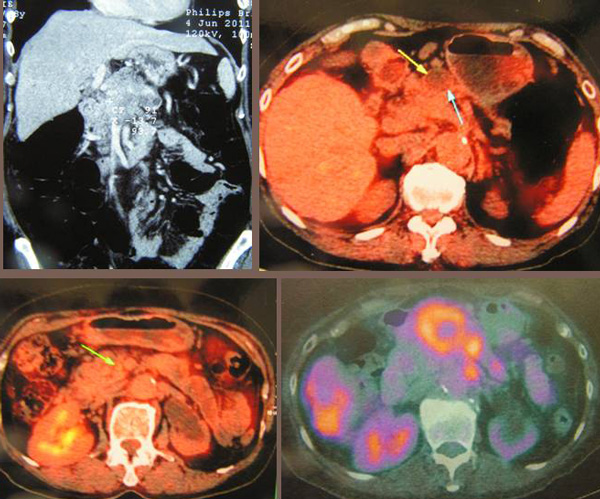

Corinna is a 51-year-old Singaporean lady. On 5 May 2012 she was diagnosed with cancer of the pancreas. From the pancreatic tail the cancer has also spread to her liver and also the posterior aspect of her stomach. The surgeon who did the biopsy told Corinna that medical treatment would not be able to cure her. Nevertheless she was asked to seek further opinion from an oncologist.

Corinna is a 51-year-old Singaporean lady banker. On 5 May 2012 she was diagnosed with cancer of the pancreas. From the pancreatic tail the cancer has also spread to her liver and also the posterior aspect of her stomach. Her blood test results on 6 May 2012 are as below.

Alkaline  Phosphatase 168  H

AST 49    H

ALT 29

GGT 174  H

Alpha-fetoprotein 2.7

CEA 1770.7   H

CA 125 2172.7   H

CA 19.9 48660.7 H